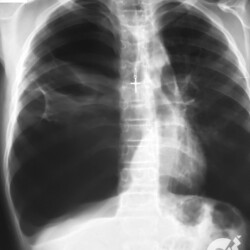

Paciente jovem, pós simpatectomia, assintomática. À esquerda conseguimos enxergar uma linha de pleura apical, sem marcas de parênquima superiormente, correto? Mas nunca podemos esquecer de ver todo o exame. No lado direito, também não tem parênquima, só gás. E existe uma linha de pleura mais discreta, mas existe. E o amigão tá lá no ápice esquerdo, o enfisema subcutâneo. Não é à toa que eu digo que é o diagnóstico mais sacana da radiologia.